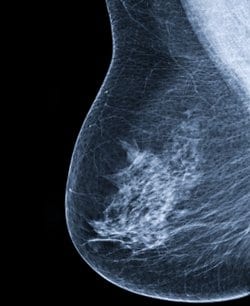

זוהו וריאנטים גנטיים חדשים הקשורים לסיכון לתחלואה בסרטן השד, הגילוי החדש כמעט ומכפיל את שיעור הוריאנטים הגנטיים הידועים כיום.

כתב העת Nature מדווח על גילויים של 65 loci הקשורים עם סיכון מוגבר להיארעות סרטן השד וזאת בעקבות עריכתם מחקרים על כלל הגנום שכללו מעל ל- 25,000 נשים ממוצא אירופאי ומזרח אסייתי, כמחצית מהנשים אובחנו עם סרטן השד.

יתר על כן, ה- Nature Genetics מפרסם כי נתגלו 7 וריאנטים נוספים הקשורים עם סיכון מוגבר להיארעות של סרטן שד שלילי לקולטנים לאסטרוגן באופן ספציפי.

החוקרים סיכמו: “הממצאים החדשים מספקים מידע נוסף בנוגע למועדות הגנטית לסרטן השד ועשויים לשפר את השימוש שנעשה בציוני סיכון גנטיים לבדיקות סקר אינדיבידואליות ולמניעה.”